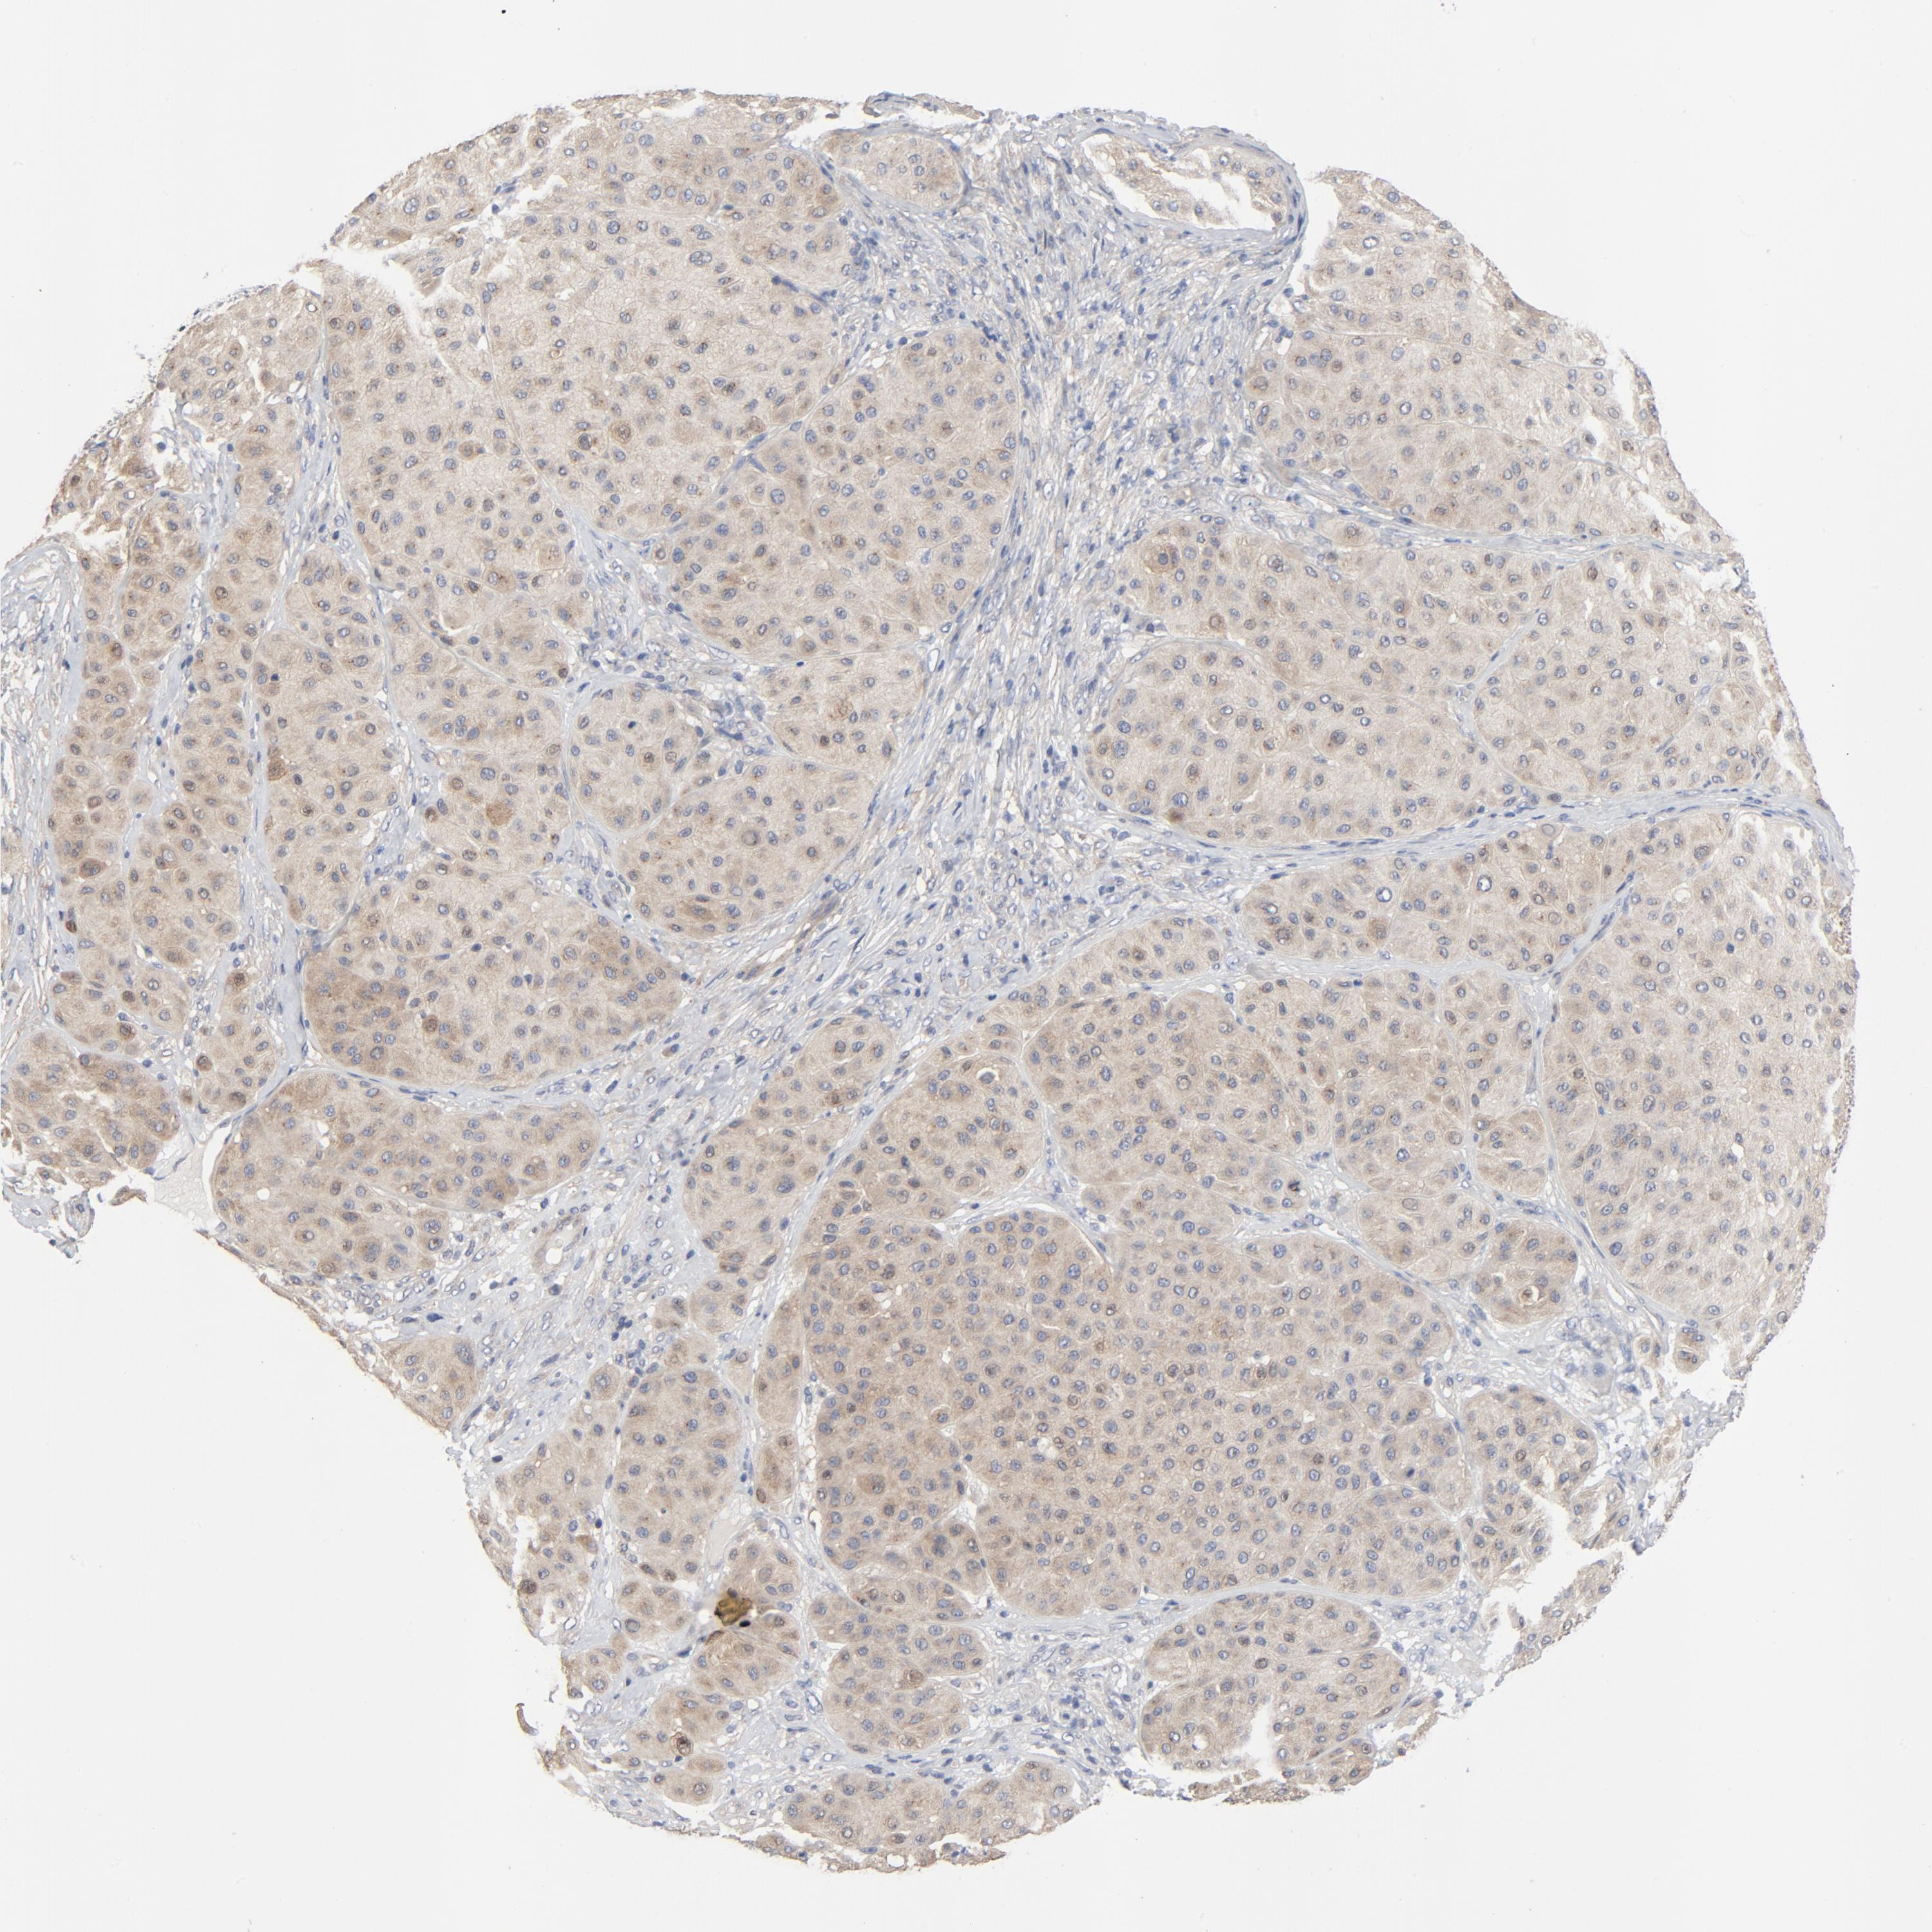

MELANOMA - Protein expressioni

A mouse-over function shows sample information and annotation data. Click on an image to view it in a full screen mode. Samples can be filtered based on level of antibody staining by selecting one or several of the following categories: high, medium, low and not detected. The assay and annotation is described here.

Note that samples used for immunohistochemistry by the Human Protein Atlas do not correspond to samples in the TCGA dataset.

Antibody stainingi

Antibody staining in the annotated cell types in the current human tissue is reported as not detected, low, medium, or high, based on conventional immunohistochemistry profiling in selected tissues. This score is based on the combination of the staining intensity and fraction of stained cells.

Each image is clickable and will lead to virtual microscopy that enables deeper exploration of all samples and also displays staining intensity scores, fraction scores and subcellular localization as well as patient and tissue information for each sample.

Antibody HPA003938

Staining

High

Medium

Low

Not detected

Intensity

Strong

Moderate

Weak

Negative

Quantity

>75%

75%-25%

<25%

None

Location

Nuclear

Cytoplasmic/membranous

Cytoplasmic/membranous,nuclear

Malignant melanoma, NOS

Malignant melanoma, Metastatic site